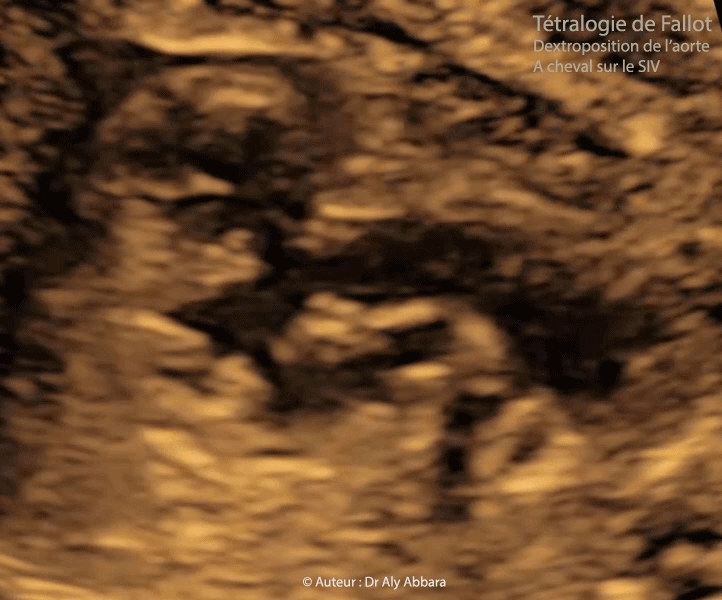

• II - Coupe analysant la continuité septo-aortique et montrant la présence de :

• Aorte dilatée et déplacée vers la droite et l'avant. Par ailleurs la crosse de l'aorte est normale, mais le canal artériel non vue ; la coupe de trois vaisseaux et trachée est impossible à mettre en évidence.

• Discontinuité septo-aortique (perte de continuité) avec la présence d'une large communication interventriculaire de type périmembraneuse sous-aortique.

• Dextroposition de l'aorte (bord antérieur de l'aorte plus à droite) faisant apparaître l'aorte comme étant " à cheval " sur le septum interventriculaire et naissant au-dessus de la communication interventriculaire.